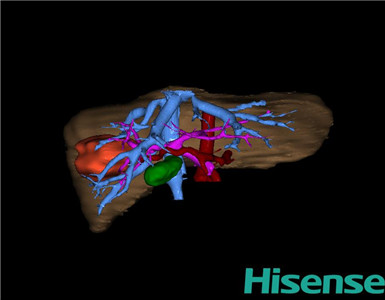

CT结果输入海信CAS系统后行3D重建:

术前三维重建及手术方案设计:

将0.625mm双源薄层CT资料的静脉期和动脉期Dicom格式文件导入海信CAS系统。

通过调节窗宽窗位调整CT序号,对肝实质,胆囊,下腔静脉,肿瘤,肝动脉、门静脉及肝静脉等进行三维重建;系统自动计算肿瘤体积和肝脏体积。模拟手术操作,自动计算切除肝体积、肿瘤体积、剩余功能性肝体积。肝脏体积为263ml,肿瘤体积为9.7ml,肿瘤体积为肝脏体积的3.9%,通过比对6-9月正常肝脏体积为257.75±51.05ml,通过术前模拟手术,精准判断切除后剩余肝脏体积能耐受,避免肝衰竭发生。

术前三维重建:

重建图片